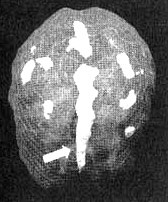

Поясная извилина

Трехмерное изображение — активный мозг, вид сверху

Глубоко в центральной части мозга, вдоль лобных долей, проходит поясная извилина. Это та часть мозга, которая позволяет вам переключать внимание с одного объекта на другой, переключаться с одной мысли на другую, видеть различные варианты решений.

Считается, что она отвечает и за ощущение безопасности.

На мой взгляд, точнее всего функции этой области мозга можно выразить термином «когнитивная гибкость».